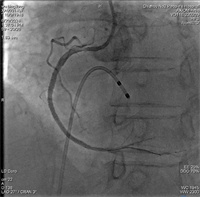

诊断急性下壁心梗,入院时已出现低血压休克症状。行冠状动脉造影提示右冠脉开口完全闭塞,导丝通过及普通球囊扩张后行血管内超声(IVUS)检查,提示近段及中段两次存在严重狭窄伴360°重度钙化,这些包绕血管的钙质就像禁锢在血管腔上的“盔甲”,使用常规球囊无法通过并扩张钙化部位,普通的球囊扩张处理只能是“以卵击石”。心血管内科吴义权副主任医师、孙春根主治医师、夏秋旺主治医师团队经全面评估后,决定给患者使用国内最新的冲击波球囊,采用血管内冲击波治疗。选择一枚3.0mm*12mm冲击波球囊分别送至右冠近段、中段钙化部位,总共发放5组冲击波,冲击波结束后,造影可见钙化部位狭窄明显减轻,经IVUS检查可见钙化环多处断裂,随后由远至近段串联植入3枚支架。整个手术过程中,患者无任何不适症状。